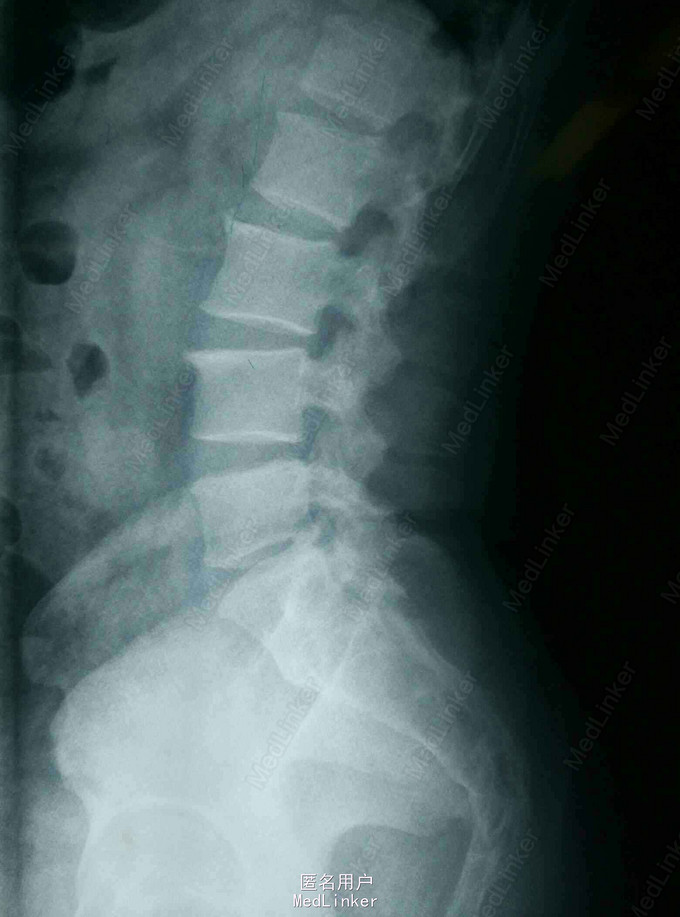

患者,男,45岁,因“腰痛伴右下肢放射痛1月,加重3天”入院。既往身体健康。

查体:脊柱无畸形,腰部L5S1间隙处轻压痛,脊柱无叩击痛,右小腿外侧及足底触痛觉减退,右下肢肌力4级,右下肢直腿抬高试验40度。 MRI提示:L5S1椎间盘脱出,髓核游离要椎管。

诊断:L5/S1椎间盘脱出(右侧) 治疗:因保守治疗效果不佳,准备行手术治疗。